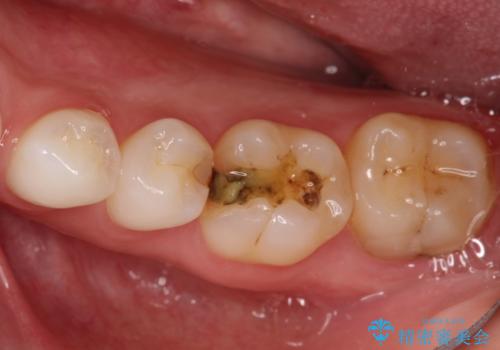

詰め物が外れた セラミックによる精密な修復

- 金属の詰め物がはずれてしまったので、精度の良いセラミックをいれたいのとのこと来院されました。

セラミックインレーにて治療することとなりました。

拡大鏡を使用して精度の高いインレーを装着しました。